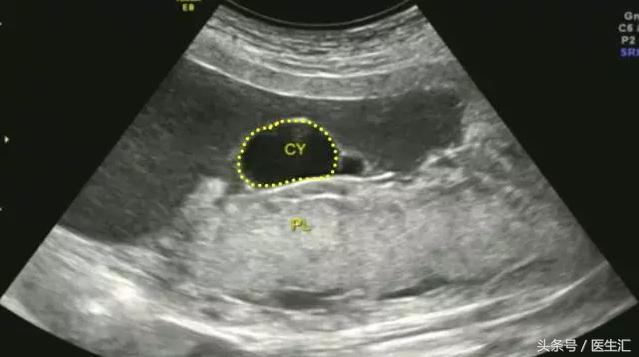

1.胎盘内血池或血窦:位于胎盘实质内,在胎盘切面内呈不规则液性暗区,内有云雾状回声呈沸水征。(见图2黄色圈内)

图2,胎盘左侧缘及右侧缘后方与宫壁间均见条状无回声区,范围约:40mm×14mm(左侧缘),36mm×9mm(右侧缘),内见密集光点浮动,似可探及静脉血流信号。